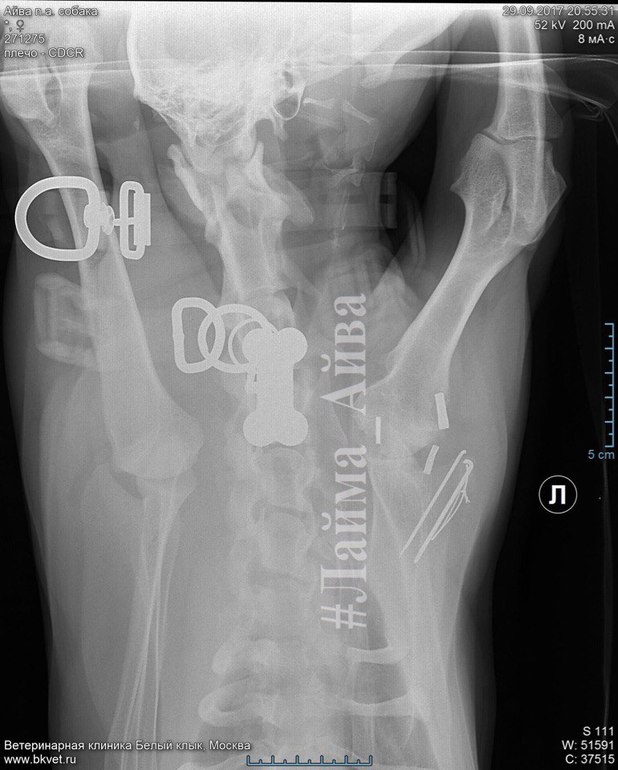

Все уже забыли про Лайму...НО СЛУЧИЛАСЬ КРИТИЧЕСКАЯ СИТУАЦИЯ, поставлен диагноз: ОСТЕОАРТРИТ плечевого сустава. АТРОФИЯ МЫШЦ плечевого пояса. НЕОБХОДИМА ОПЕРАЦИЯ...😭😭😭 Лайма хромает и ей больно...

Я давно не просила вас о помощи ни с передержкой,ни с кормом,пыталась справляться своими силами,понимая,что у всех куча животных более больных и тяжелых... Кто знает историю Лаймы с самого начала,помнит,когда мы ее нашли,лапа была сломана,прооперировали,но вот спустя год последствия на эту же лапу продолжаются... СРОЧНО НУЖНА ОПЕРАЦИЯ АРТРОДЕЗ ЛЕВОГО ПЛЕЧЕЛОПАТОЧНОГО СУСТАВА❗️ Принимал доктор Комаров А.А.

клиника "Белый Клык"